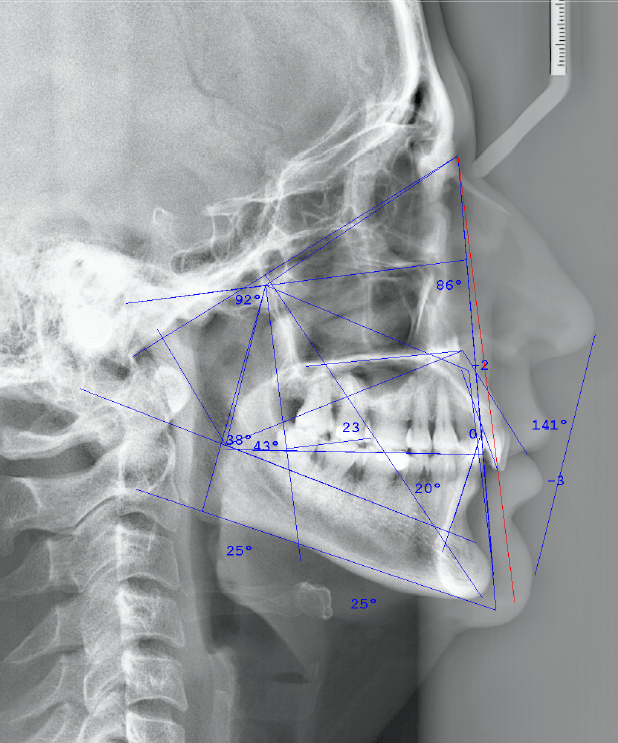

RADIOGRAFÍA Y TOMOGRAFÍA CONE BEAM ODONTOLÓGICA

CRYT Centro Radiológico y Tomográfico Odontológico / Dental en Salta

- Radiología

- Ortopantomografía